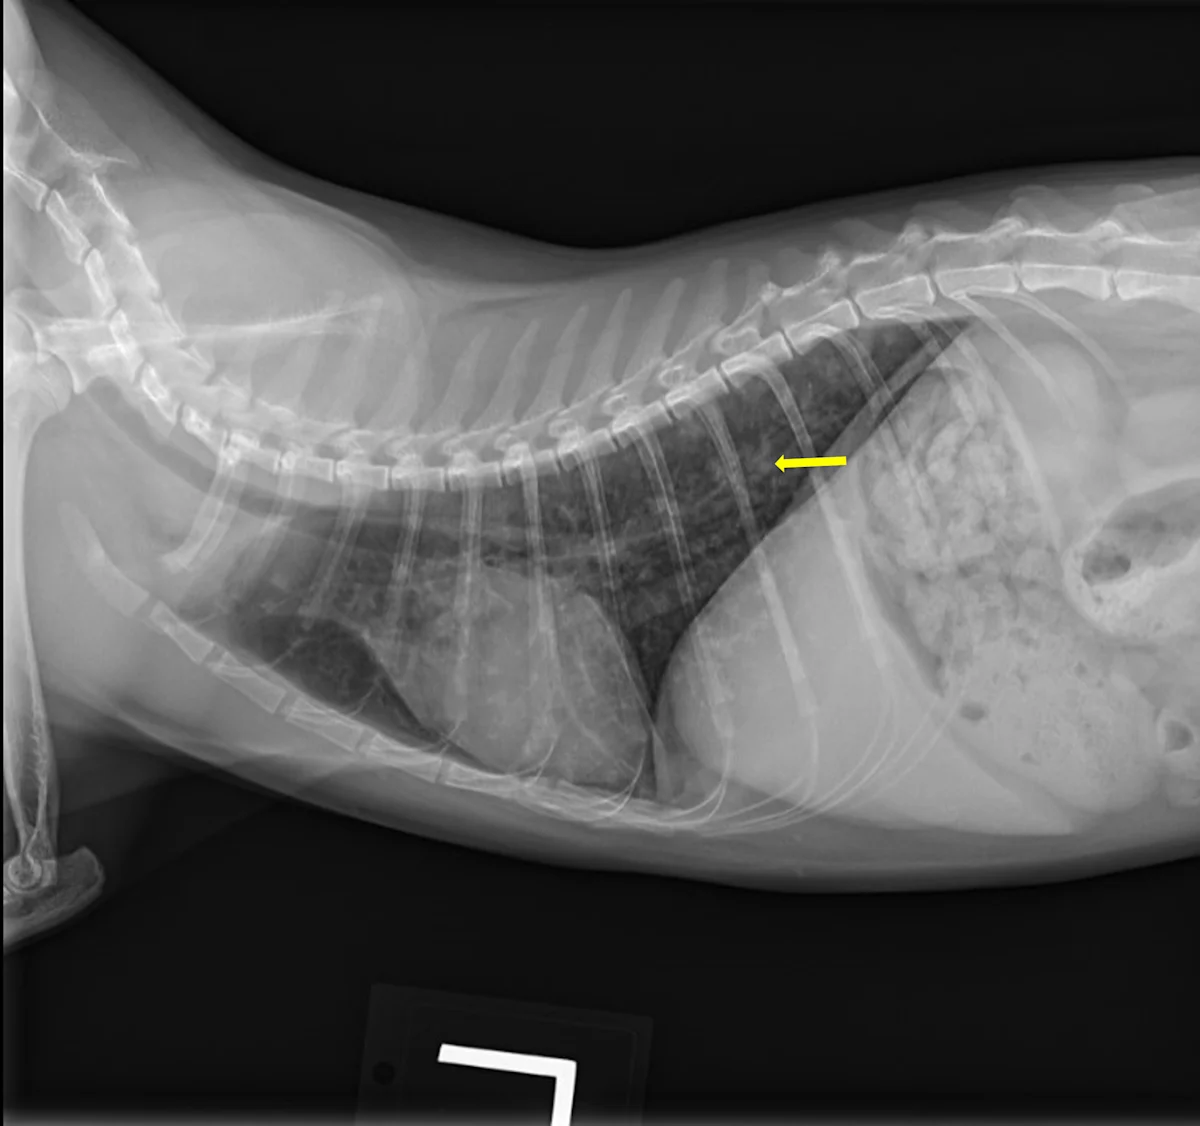

Butorphanol (0.2 mg/kg IV) was administered for sedation to obtain 3-view thoracic radiographs (left lateral, right lateral, ventrodorsal). Results revealed diffuse pulmonary nodular changes with an underlying bronchointerstitial pattern (Figure 1). Fungal pneumonia, parasitic pneumonia, neoplasia, and eosinophilic inflammatory disease were the most likely differentials for this pattern.

FIGURE 1 Left lateral (A), right lateral (B), and ventrodorsal (C) thoracic radiographs at the time of initial diagnosis. Diffuse pulmonary nodular changes with an underlying bronchointerstitial pattern can be seen.